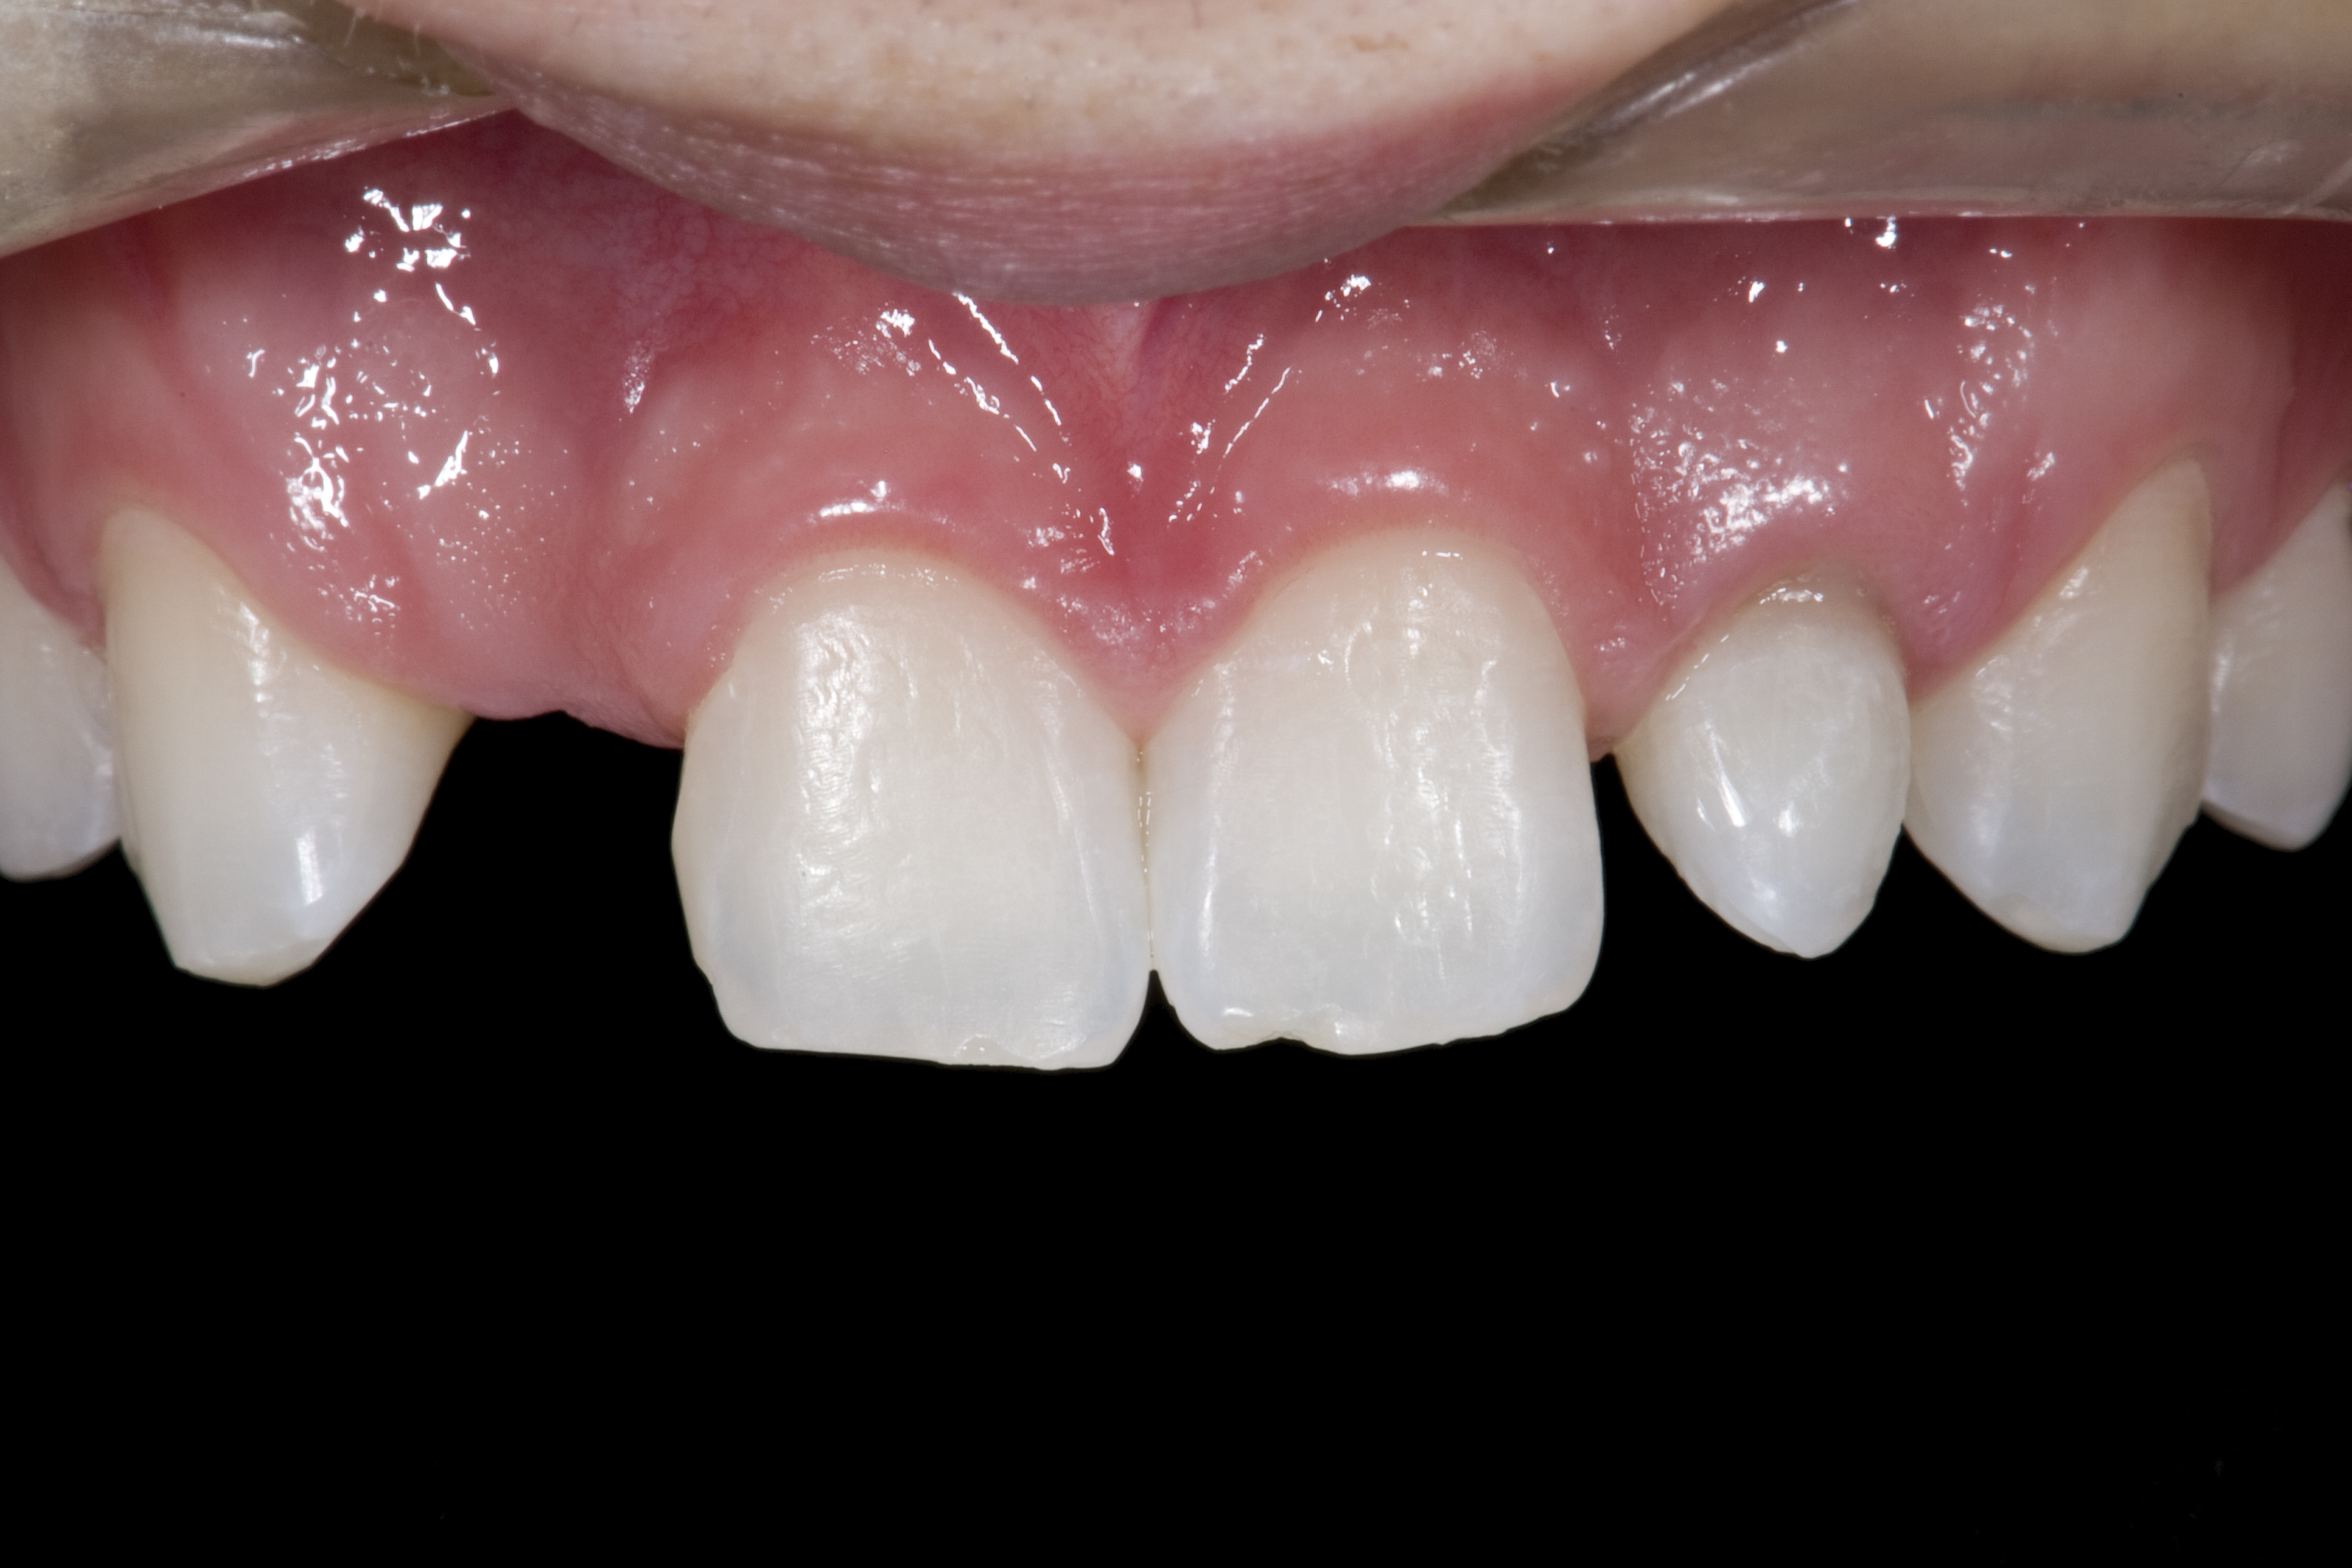

(20.) Facial view of final single-wing, modified zirconia resin-bonded bridges.

Figure 20

(21.) Smile view.

Figure 21

When the patient returned, the fit was evaluated in the mouth. Once verified, the internal surface of the framework was etched with a 9.5% hydrofluoric acid for 90 seconds and then salinized. After etching the enamel surface with phosphoric acid for 30 seconds and applying the primer (Single Bond Plus, 3M ESPE) to both the internal surface of the framework and the enamel, the zirconia bridge was bonded with a dual-cure resin cement (RelyX™ ARC, 3M ESPE). After the procedure, the patient ended up with a long-term, high-strength esthetic restoration advantaged by the bonding potential of fledspathic ceramic (Figure 20 through Figure 24). Six years after placement, the prosthesis had remained in place with no complications.